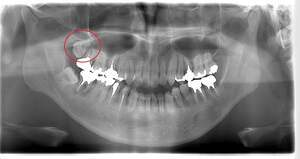

右上の親知らず抜歯症例

- 抜歯前写真(レントゲン)

- 抜去歯の写真

| 年齢 | 40代・男性 |

|---|---|

| 主訴 | 右上8番抜歯したい |

| 治療期間 | 1日 |

| 費用 | 2,620円 (2022年12月現在) |

| 担当者所見 | レントゲンでは上顎洞に親知らずが突き刺さっているように見えましたが、抜歯後穿通は見られませんでした。 抜歯後2、3日をピークに腫れ、発熱、内出血が出ることがありますが、痛み止めを飲んでしのげる程度がほとんどです。 抜歯後は細菌感染のリスクがあるため抜いたところを舌や指で刺激しないよう注意してもらいます。 |

| リスク・副作用 | 抜歯の際、上顎洞に穴が空くことがありますが、空いた穴が小さく炎症を起こさなければ自然に塞がります。 抜歯後2,3日が腫れのピークになり発熱、内出血が出ることがありますが、痛み止めを飲んでしのげる場合がほとんどです。 抜歯後は細菌感染のリスクがあるため抜いたところを舌や指で刺激しないように注意してもらいます。 激しくゆすぎすぎるとドライソケットになるため、うがいは優しくするようにしてもらいます。 |